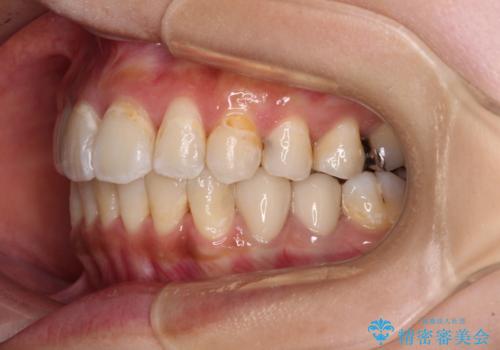

- 虫歯が多く、磨きにくい歯並びを改善したいとのことで来院された患者様です。

歯列は叢生が認められる程度でしたが、やや前突感があったので、少しでも口が閉じやすくなるように仕上げる方針としました。

神経を取り除かれている歯3本以外にも虫歯が認められたため、事前に処置を行い、インビザラインにて矯正治療を行うこととしました。

神経が取り除かれている歯は、クラウンによる補綴治療が必要であるため、矯正治療後にオールセラミッククラウンにて補綴治療を行うこととしました。

歯磨きしやすくなるとともに、飛び出していた前歯も引っ込めて整えることができました。